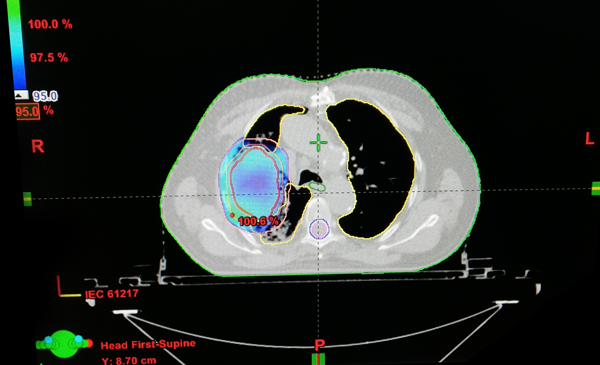

Dr. Mitra has extensive training in Intracranial Stereotactic Radiotherapy, Radiosurgery, Stereotactic Body Radiotherapy and Brachytherapy especially in gynecologic Tumors. Dr. Mitra is a specialist in modern techniques of radiation oncology namely in Intensity Modulated Radiotherapy (IMRT), Image Guided Radiotherapy (IGRT), Conformal Radiotherapy and Palliative Radiotherapy.